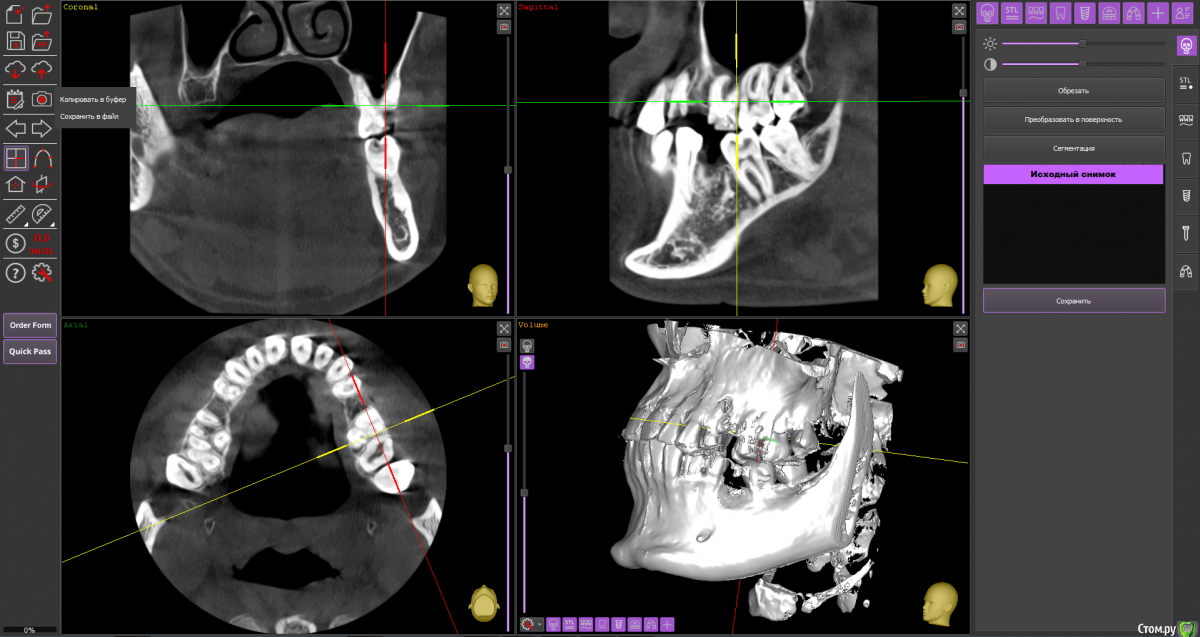

Michaelpupkins Опубликовано 20 января, 2021 Поделиться Опубликовано 20 января, 2021 Запустил свои зубы в 26 лет, расписали помимо терапии только план лечения с имплантацией на 340000₽, так ли это??? Вместе с терапией на 800000₽ вообще написали до осмотра в реале.Так ли это? Кто может написать свой план лечения предположительно, спасибо. Прикрепляю ссылку на КТ. Снимок большего разрешения, потому что делал не в России. https://yadi.sk/d/odR9T8X4dHgTCQ Ссылка на комментарий

wladdX Опубликовано 20 января, 2021 Поделиться Опубликовано 20 января, 2021 (изменено) Прилагаемый план вполне может иметь место, понятно, что нужен очный приём, по одним снимкам судить можно только приблизительно. Финансовые вопросы мы не обсуждаем, но мне не показалось, что имеется какое-либо завышение что ли, для СПБ вполне себе. "Снимок большего разрешения, потому что делал не в России" - никакого он не большого разрешения, размер .dcm кадра всего лишь 492 КБ, что является обычным средним рамером и количество кадров обычное. О большом можно говорить где-то начиная с 705 КБ. Изменено 20 января, 2021 пользователем wladdX 1 Ссылка на комментарий